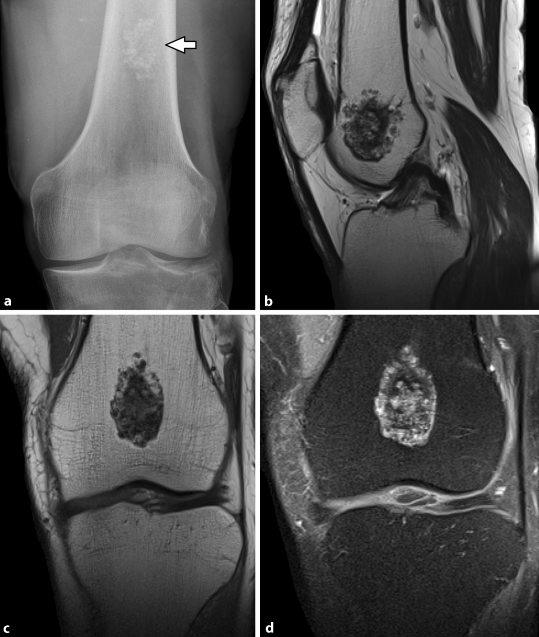

Chondroblastom Springerlink

Tumorahnliche Knochenveranderungen Springerlink